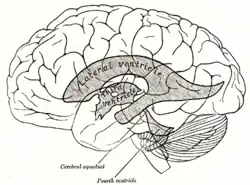

Drawing of a cast of the ventricular cavities, viewed from the side.

The cerebral aqueduct (aqueduct of the midbrain, aqueduct of Sylvius, Sylvian aqueduct, mesencephalic duct) is a small, narrow tube connecting the third and fourth ventricles of the brain.[1][2] The cerebral aqueduct is a midline structure that passes through the midbrain. It extends rostrocaudally through the entirety of the more posterior part of the midbrain. It is surrounded by the periaqueductal gray (central gray), a layer of gray matter.[3]

The cerebral aqueduct is roughly circular in transverse section, and measures 1-2 mm in diameter.[3] It is 15 mm long and is commonly subdivided into a pars anterior antrum, and pars posterior.[2]

Rostrally, it is continuous with the third ventricle, commencing just inferior to the posterior commissure.[3]

Caudally, it is continuous with the fourth ventricle at the junction of the mesencephalon and pons.[3]

The cerebral aqueduct acts as a canal that passes through the midbrain. It connects the third ventricle with the fourth ventricle so that cerebrospinal fluid (CSF) moves between the cerebral ventricles and the canal connecting these ventricles.[5]